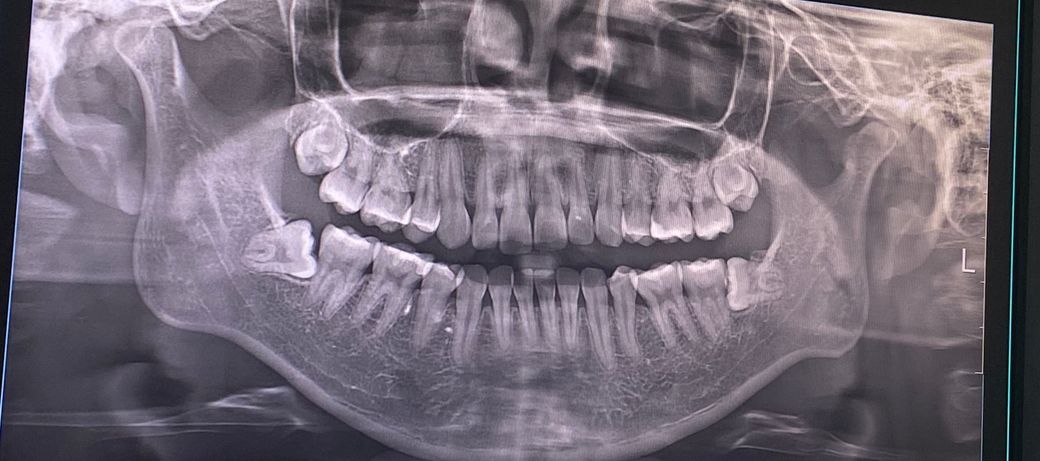

매복사랑니 발치 난이도랑 발치 시간 궁금해요

곧 사랑니 발치를 앞두고 있는데요, 너무 무섭고 긴장되서 여쭤봅니다😢 동네 대학병원에 매복치아 발치 전문으로 하시는 교수님 예약해두었구요. 교수님께서는 마취주사부터 봉합까지 30~45분 걸린다는데… 이정도면 많이 어려운 난이도인가요??ㅠㅠ

이번주에 위아래 두개 그리고 다음주에 나머지 두개뽑을 예정이에요..